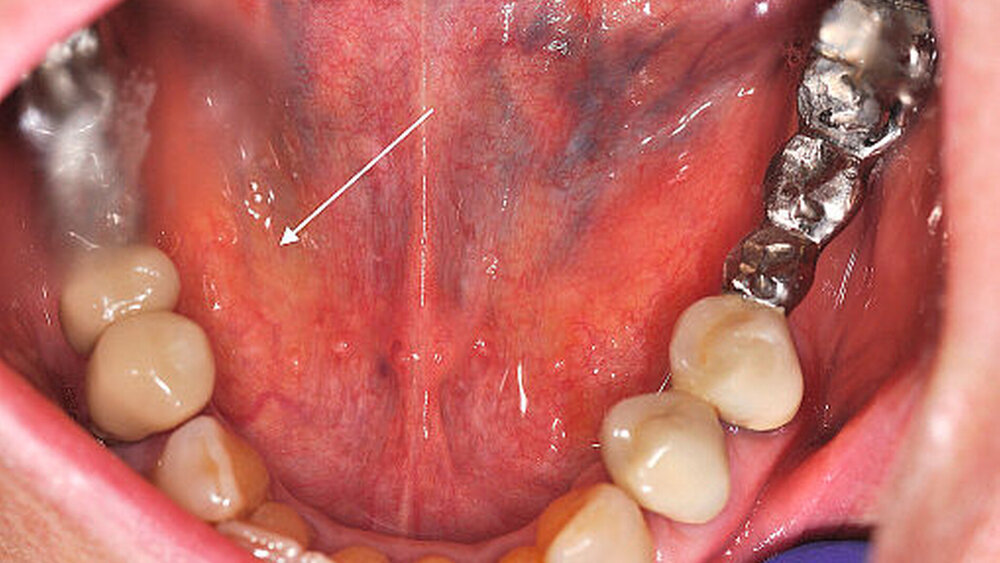

Aufgrund des ausgeprägten Lokalbefunds (Abbildung 2) konnte die Verdachtsdiagnose klinisch durch die bimanuelle Palpation des Mundbodens bestätigt werden. Die Bildgebung mittels Sonografie komplettierte das diagnostische Procedere (Abbildung 3). Nebenbefundlich nahm die Patientin aufgrund von anamnestisch rezidivierenden, tiefen Beinvenenthrombosen Rivaroxaban (Xarelto®, 20 mg, 1–0–0) zur Antikoagulation ein.

Bei klinischem, sonografischem und radiologischem Verdacht auf einen im Ausführungsgang der Glandula submandibularis rechts gelegenen und im hinteren Mundboden lokalisierten Speichelstein, erfolgte nach ausführlicher Aufklärung der Patientin die operative Steinentfernung.